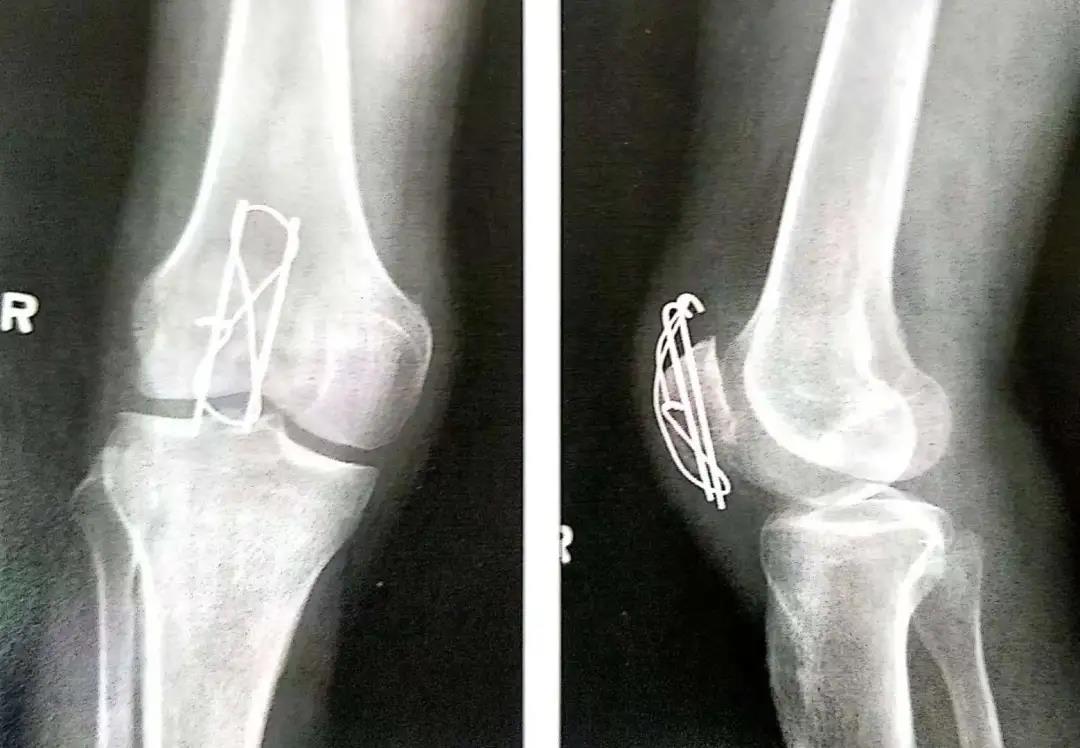

- 顺行或逆行打入克氏针。

- 克氏针或螺丝钉应在髌骨前皮质面下大约5mm打入,在骨质内冠状面和矢状面上相互平行。

- 在穿过骨折线之前,可用术中透视(正位和侧位)直视下或将手指伸到髌骨下触摸的方式来确保骨折已复位。

- 使用14或16号的导管作为环扎线的通道。将其穿过临近骨质的四头肌腱和髌韧带内以尽量减少由钢丝所致的软组织损伤。钢丝尽可能接近髌骨,这一点很重要。

- 然后以导管作为通道将18号钢丝穿入软组织内。